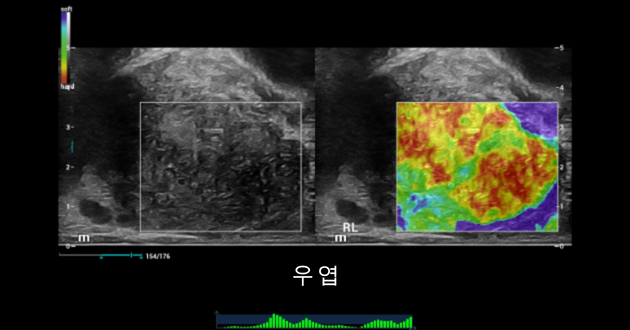

전립선 우엽 초음파 소견:

형상1, 형상2. 2D 초음파 검사에서 우엽 주변부 및 불규칙한 캡슐에서 의심스러운 혈관 과다성 저에코 결절이 발견됨.

Prostate shearwave right lobe

형상4. 우엽의 탄성 초음파는 저에코성 결절 소견과 관련된 KaMoi Score NO.5, E/B 비율>1의 상당히 경화된 영역을 보여줌.

형상6. 우엽 전립 부위 경화 측정 결과